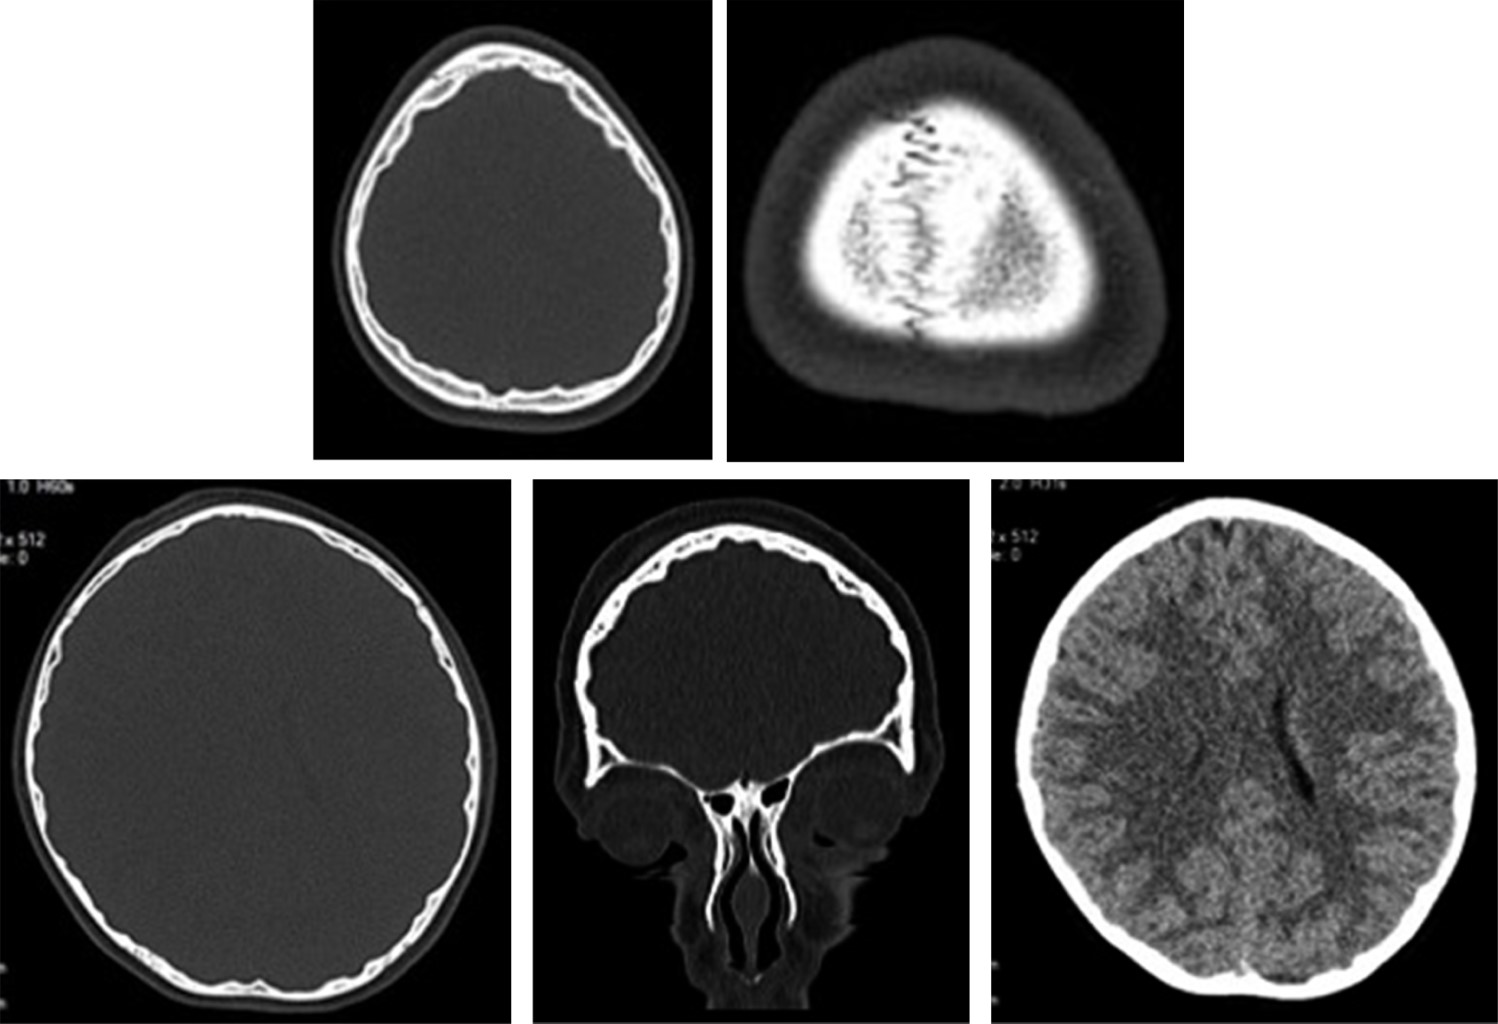

En la Figura 1 se muestran las radiografías de cráneo donde se observan múltiples imágenes radiolúcidas de tipo geográfico en todos los huesos de la bóveda craneal, con distribución simétrica, generalizada, delimitadas por imágenes lineales radiopacas bien definidas. Estos hallazgos radiográficos se consideran que, en conjunto, imitan la distribución y aspecto del patrón de giros y circunvoluciones cerebrales.

Sin embargo, el médico de guardia decide realizar tomografía simple de cráneo, en la cual se confirman que se trata de suturas normales, sin lesiones líticas o blásticas ni trazos de fractura; el encéfalo es de características normales, descartando datos de cráneo hipertensivo (Figura 2). Solamente se identificó adelgazamiento multifocal y geográfico de la tabla interna del cráneo, que asemeja la forma, distribución y anatomía al patrón de giros, surcos y circunvoluciones cerebrales. Los huesos del macizo facial y vértebras cervicales son normales. Con estos datos se confirma que se trata de un "cráneo en cobre batido" o "cobre martillado".

Figura 1

Figura 2